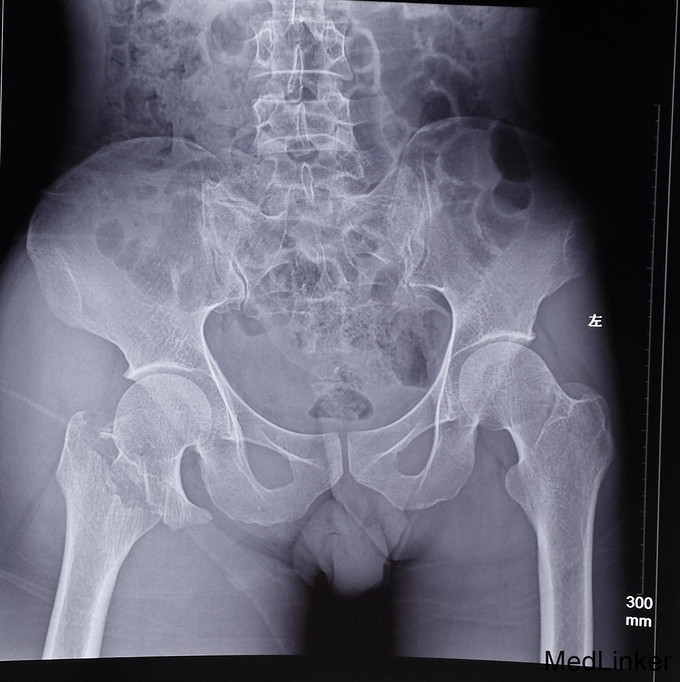

患者,女,73岁,从床上翻身摔下时,腿部突然活动受限,脚无法着地,马上送往医院进行检查。

1、观之患肢有轻度屈髋屈膝及外旋畸形2、髋部除有自发疼痛外,移动患肢时疼痛更为明显。3、给予X光片检查。4、给予血尿常规和肝肾功能、心电图检查。

光片提示:该患者发生发生股骨颈基底部移位骨折。急诊:静脉滴注消炎。两天后对患者进行了复位内固定手术。